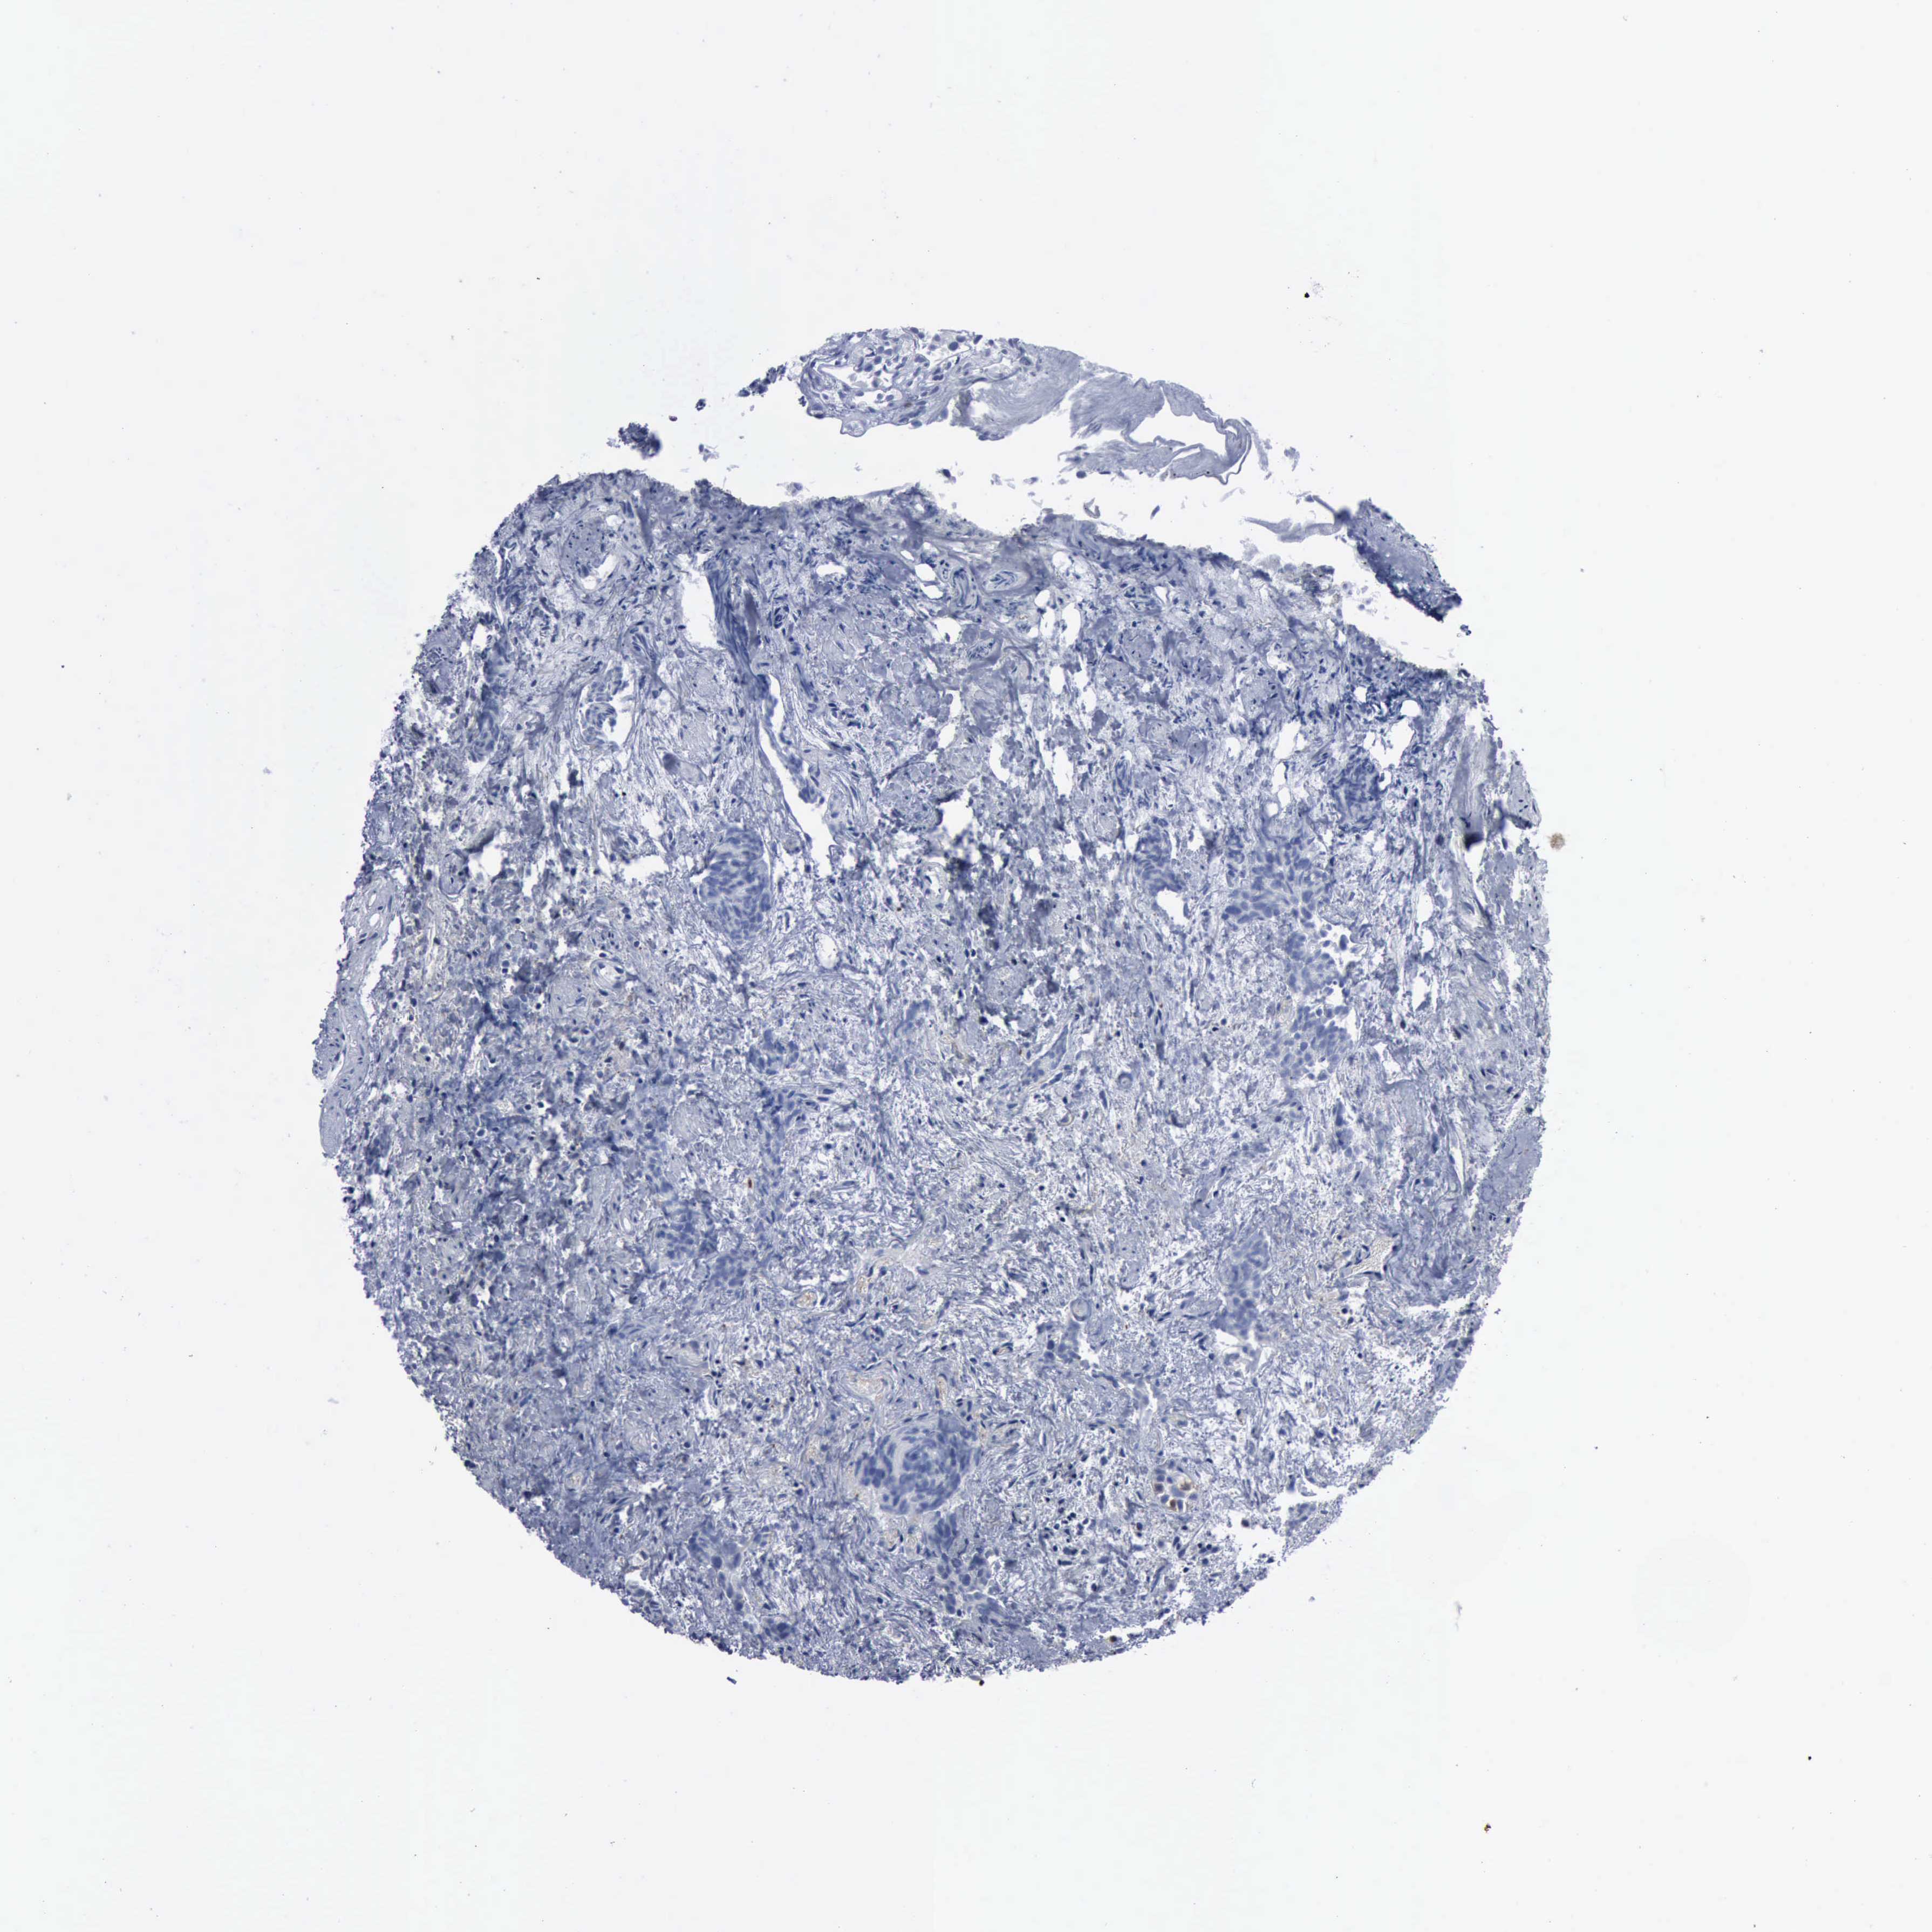

UROTHELIAL CANCER - Protein expressioni

A mouse-over function shows sample information and annotation data. Click on an image to view it in a full screen mode. Samples can be filtered based on level of antibody staining by selecting one or several of the following categories: high, medium, low and not detected. The assay and annotation is described here.

Antibody stainingi

Antibody staining in the annotated cell types in the current human tissue is reported as not detected, low, medium, or high, based on conventional immunohistochemistry profiling in selected tissues. This score is based on the combination of the staining intensity and fraction of stained cells.

Each image is clickable and will lead to virtual microscopy that enables deeper exploration of all samples and also displays staining intensity scores, fraction scores and subcellular localization as well as patient and tissue information for each sample.

Antibody HPA000962

Antibody HPA004119

Urothelial carcinoma, High grade